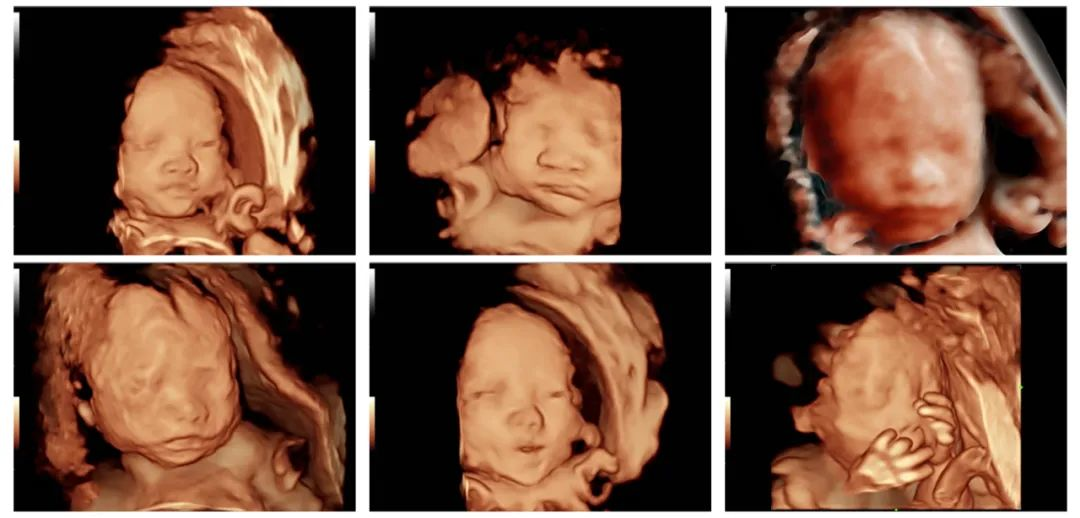

1.非医学需要的胎儿性别鉴定:除医学需要的原因外,医疗机构和胎儿父母违反相关法律法规的规定,采用做超声、采血检测等手段进行胎儿性别鉴定的行为。

1.医疗机构、非法行医机构或个人利用检验或超声技术等手段进行非医学需要的胎儿性别鉴定和选择性别人工终止妊娠。